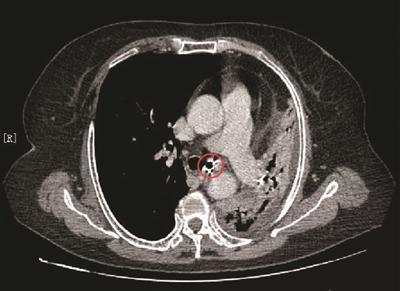

CT片上的金属影原来是颗假牙。

在术前评估中,省中医院的专家们发现病情有些奇怪。“虽然检查发现胸骨后确有巨大甲状腺肿并压迫了气管,但根据我们多年的临床经验,如此巨大甲状腺肿不至于引起患者咳嗽十几年,严重到CT片上看不到左肺影像。”普外科副主任医师戴洪山介绍说,“更加奇怪的是,患者左支气管入口处有金属影,不像之前其他医院认为的血管钙化影。”

带着疑问,医生多次询问李阿姨,然而她一口咬定没做过肺部手术,也从没有误吞过异物。为了谨慎起见,医院组织放射科、呼吸科等多学科专家联合会诊,专家一致认为,患者左支气管内有1.5厘米的金属影,异物滑落的可能性很大。